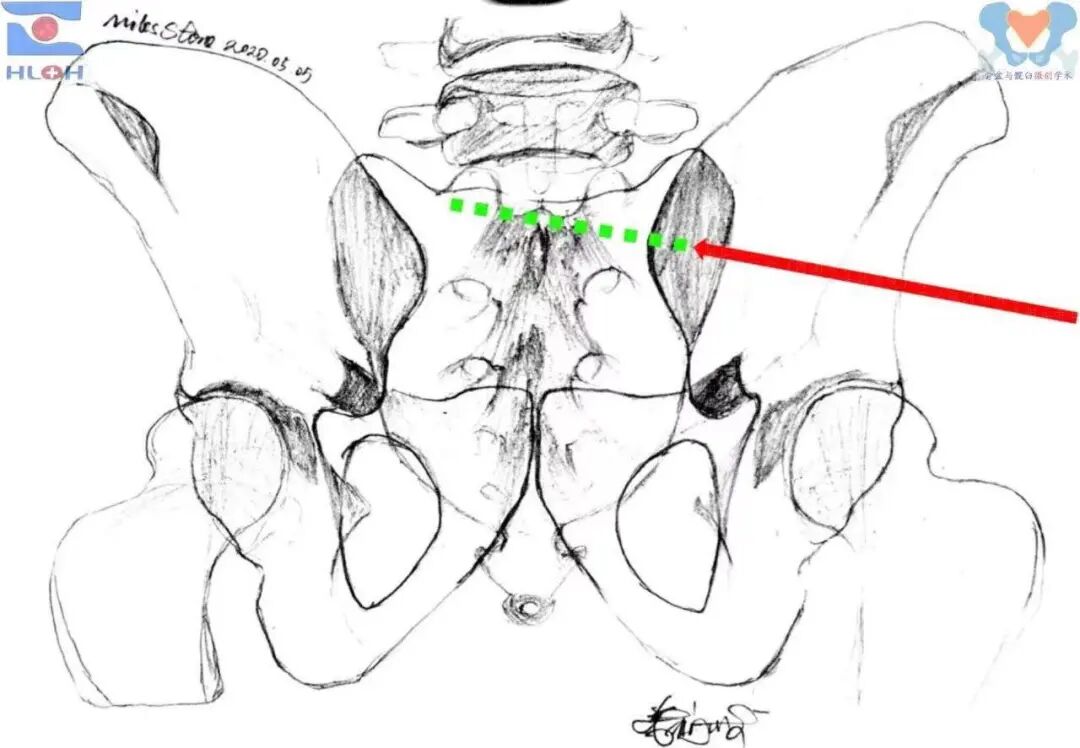

针对这一痼疾,我们有着支点之心的创伤骨科医者,只要遵循事实、发现规律并稍做变通就可以迎刃而解之。在术前骨盆轴向CT断层图像上,我们规划骶髂螺钉置入的过程中发现两个基本事实,一是骶髂螺钉完全位于骨盆横断面内,二是除了进钉点之外,唯一能限制骶髂螺钉位置的参数就是螺钉与骨盆冠状面(双侧髂后上棘的连线)的夹角。

骨盆轴向断层CT图像上骶髂螺钉置入的规划